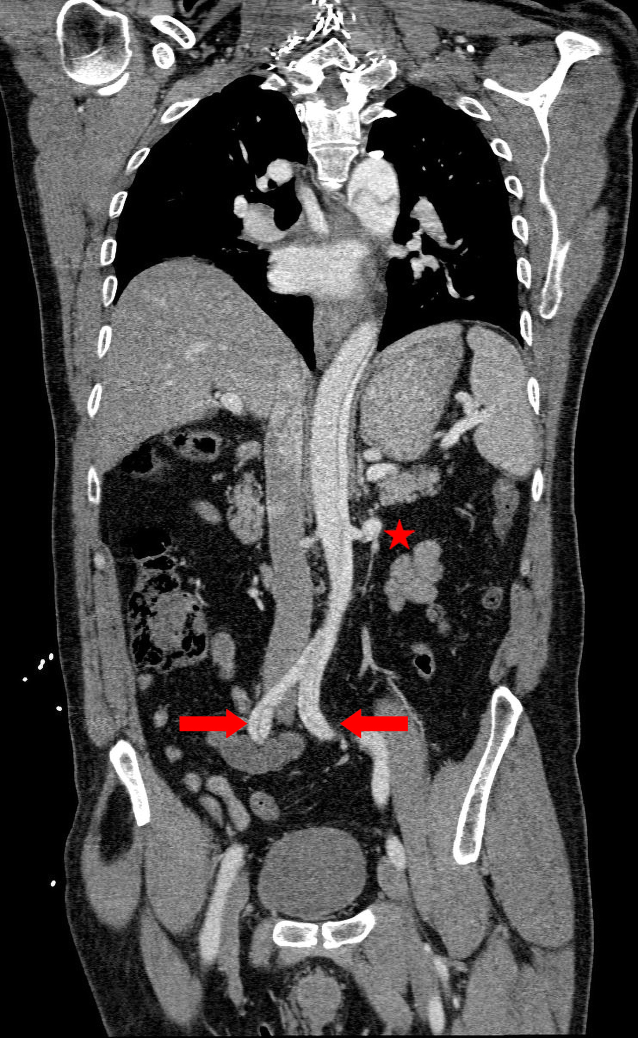

Der Beginn der Dissektion lag auf Höhe des Aortenbulbus (Abb. 2). Die Dissektion dehnte sich bis in die Iliakalgefäße aus (Abb. 3). Die Koronarien und die distalen hirnversorgenden Gefäße waren regelrecht kontrastiert. Zudem ergab sich kein Anhalt auf eine Endorganischämie oder ein Hämatoperikard. Aus ärztlicher Sicht ergab sich eine klare Indikation zur sofortigen operativen Versorgung.

Abb. 3

Koronarer Schnitt: Beteiligung der linken Nierenarterie (Stern) und der Iliakalgefäße (Pfeile)

Bild vergrößern